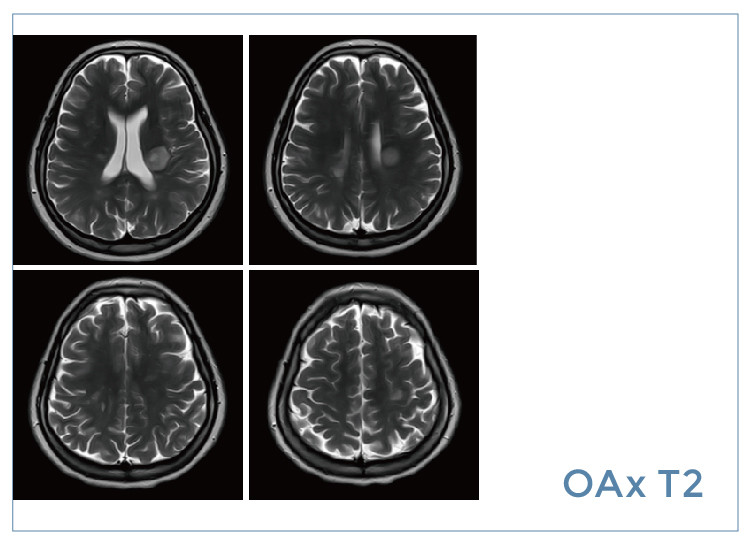

【朗润影像档案】磁共振影像病例分享(编号20190830)